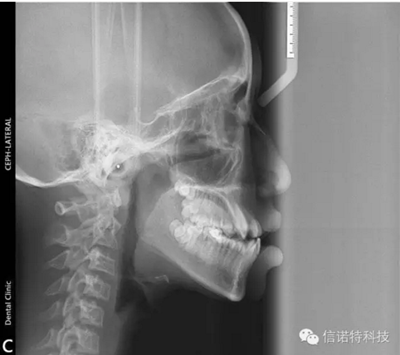

常用X線頭影測量的標(biāo)志點

節(jié)選自《口腔正畸學(xué)》主編:傅民魁 林久祥

蝶鞍點(S.sella):蝶鞍影像的中心。這是常用的一個顱部標(biāo)志點,在頭顱側(cè)位片上較容易確定。

鼻根點(N.nasion):鼻額縫的最前點。這是前顱部的標(biāo)志點,代表面部與顱部的結(jié)合處。有些X線片上,此點顯示不太清楚,是因為其形態(tài)不規(guī)則骨縫形成角度之故。

耳點(P.porion):外耳道之最上點。頭影測量上常以定位儀耳塞影像之最上點為代表,稱為機(jī)械耳點。但也有少數(shù)學(xué)者使用外耳道影像之最上點來代表,則為解剖耳點。

顱底點(Ba.basion):枕骨大孔前緣之中點。一般此點較易確定,常作為后顱底的標(biāo)志。

Bolton點:枕骨髁突后切跡的最凹點。

這些標(biāo)志點中,有些是在正中矢狀面上,是單個的點。如鼻根點、蝶鞍點等。而有些則是雙側(cè)的點,如下頜角點,關(guān)節(jié)點等。若由于面部不對稱而使兩側(cè)之點不重疊時,則取二點間的中點作為校正的位置。